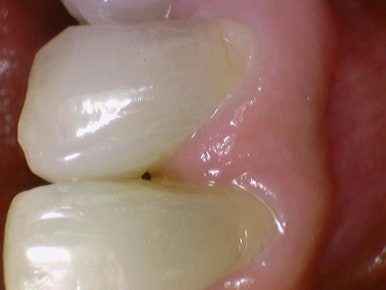

치경부마모(치아 목부위 패인 부위, 시린부분) 레진

치경부 마모 레진치료